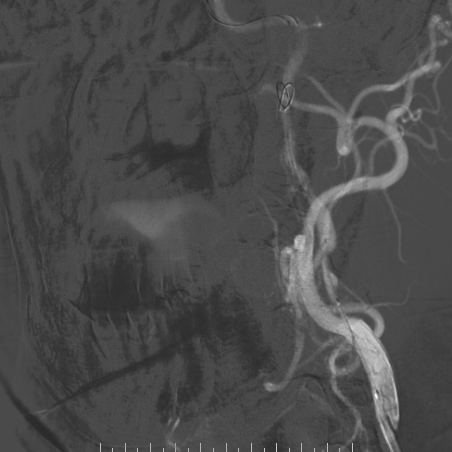

心脑联合造影

-- 左侧颈内起始部重度狭窄

-- 路途引导下,FilterWire EZ保护伞顺利通过狭窄段至左侧颈内动脉岩骨水平段,顺利释放保护伞

--沿保护伞导丝引入波科4mm*30mm-Sterling球囊跨狭窄段扩张后,交换9mm*40mm-Wallstent支架经波科7F导引导管顺利到达狭窄段,跨狭窄段缓慢平稳释放。

-- 支架释放后残余狭窄稍高,再次交换引入波科4mm*30mm-Sterling球囊行支架内后扩张,使用5F 125cm多功能回收保护伞,复查造影示狭窄明显改善,前向血流通畅。

-- 术后即刻正侧位造影示左侧颈内起始部狭窄明显改善,支架内血流通畅,远端分支显影正常。